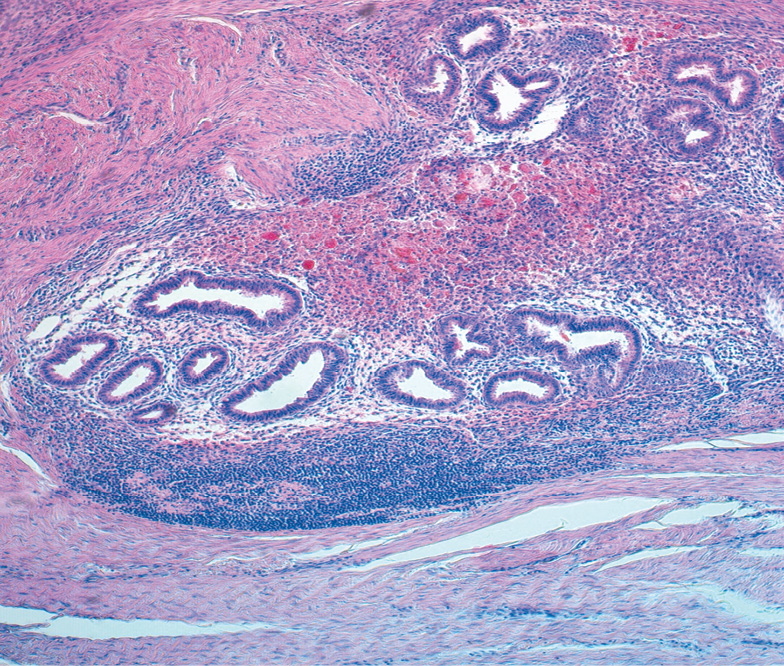

In a morphological study, postoperative scar endometriosis was manifested by a classic histological presentation characteristic of endometrioid disease, namely, a combination of glands lined with endometrial type epithelium with endometrial cytogenic stroma, old and recent hemorrhages, hemosiderin deposition, and accumulation of hemosiderophages (Fig. 4). Pronounced lymphomacrophage infiltration of the cytogenic stroma and soft tissues immediately adjacent to the endometriosis focus were noteworthy. In some cases, lymphomacrophage infiltration was focal in the form of microabscesses. In 2 (9.5%) of 21 cases, suture material remnants were detected between the endometriosis foci with granuloma formation surrounded by foreign bodies. Hemosiderin deposits were revealed in the lumen of the glands, cytogenic stroma, and surrounding tissues and caused active migration of free stromal cells, followed by the formation of hemosiderophages.

Fig. 4. The focus of the postoperative scar endometriosis. Hematoxylin-eosin stain, zoom ×100

Рис. 4. Очаг эндометриоза послеоперационного рубца. Окраска гематоксилином и эозином, увеличение ×100